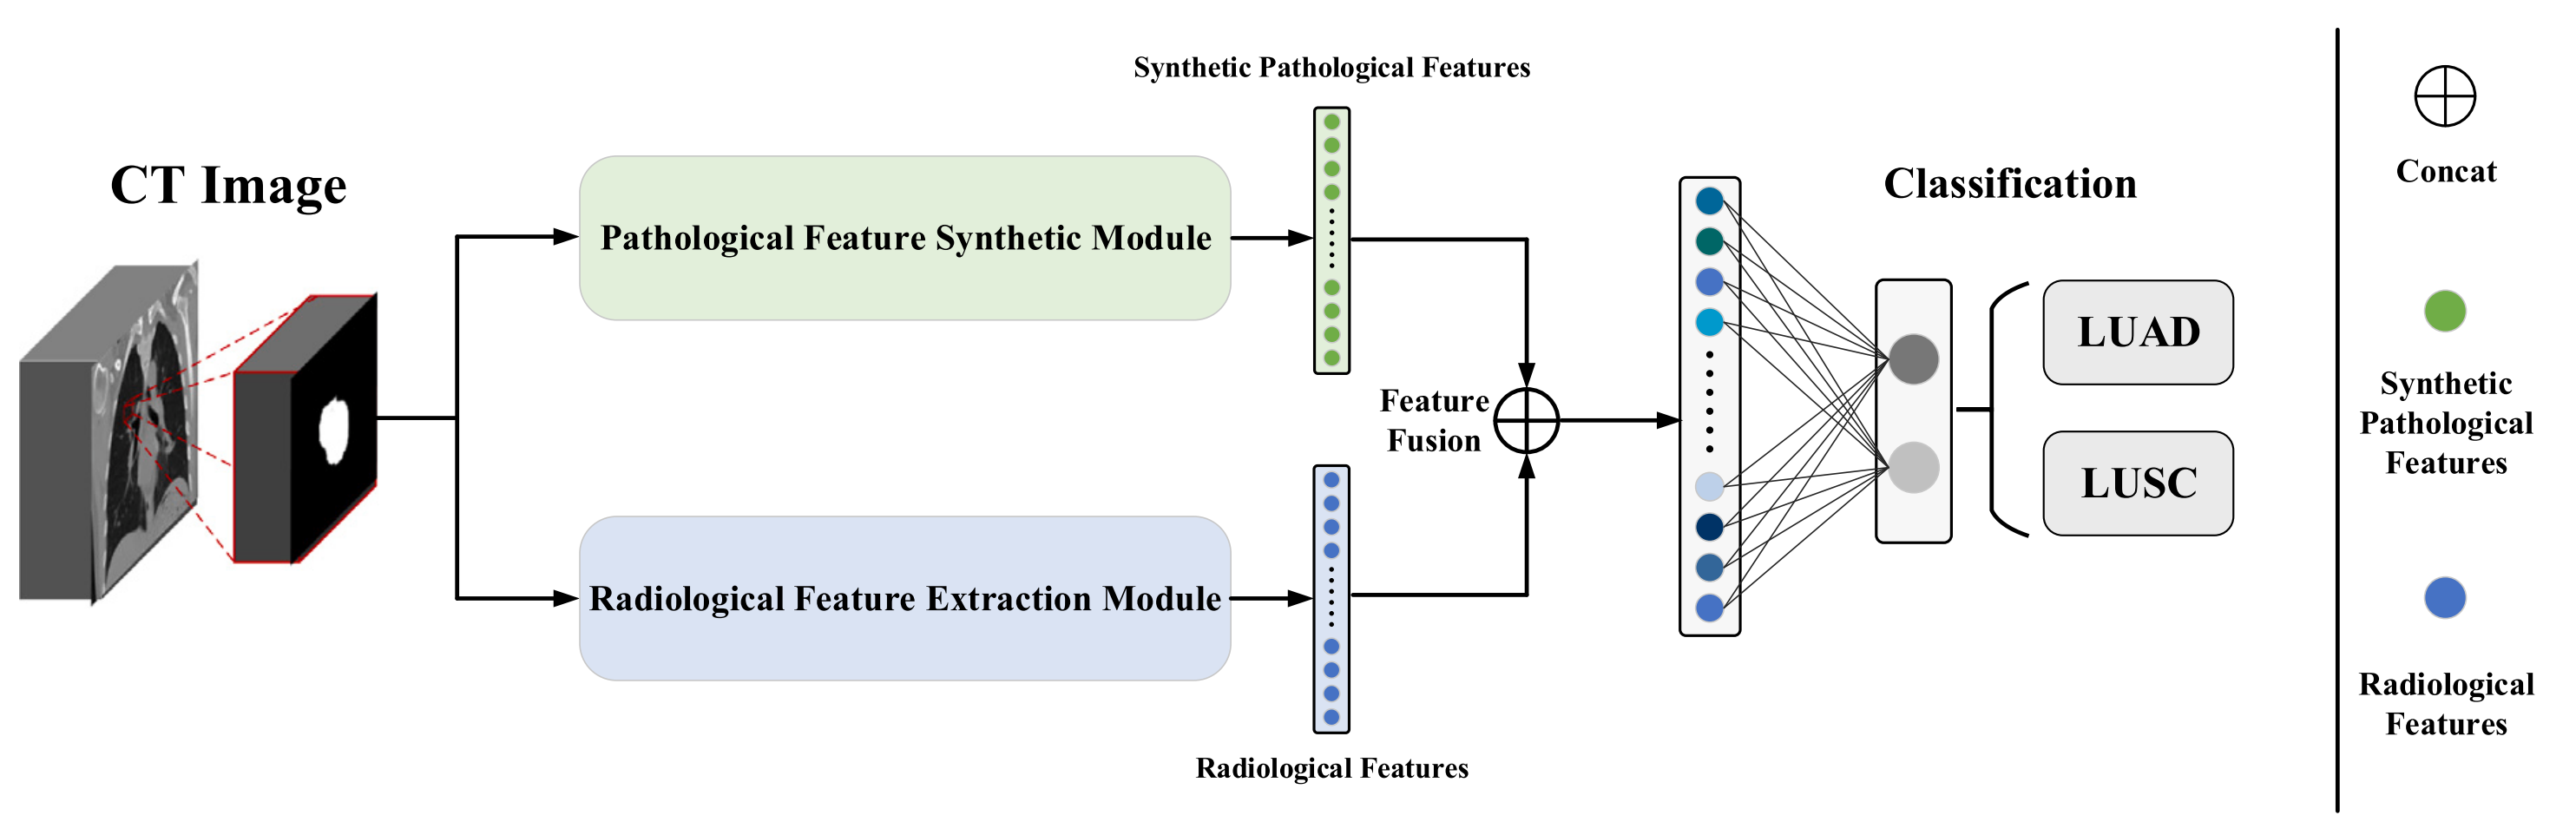

SGHF-Net(自生成混合特征网络)的流程图——基于CT图像的新型分类模型。

SGHF-Net 通过结合病理学特征(pathological features)和放射学特征(radiological features)来提高肺癌亚型的分类准确性。

特征提取:

- 𝑓p 代表从病理图像(Pathological Images)中提取的特征,这些特征是通过病理特征合成模块(Pathological Feature Synthetic Module, PFSM)生成的,该模块能够从CT图像中定量映射跨模态关联,生成类似于病理图像的高级特征。

- 𝑓r 代表直接从CT图像中提取的放射学特征(Radiological Features),这是通过放射学特征提取模块(Radiological Feature Extraction Module, RFEM)完成的。

特征融合:

- 𝐹(⋅) 表示融合模块(Fusion Module),它的作用是将病理学特征 𝑓p 和放射学特征 𝑓r 结合起来。这个融合过程旨在整合两种模态的信息,以生成更全面的特征表示,这些表示能够更好地捕捉肺癌的病理特性。

分类:

- 𝐶(⋅) 表示分类组件(Classification Component),它利用融合后的特征来执行肺癌亚型的分类任务。分类组件的输出是模型对CT图像中肺癌亚型的预测。

整体流程:

- 输入:模型的输入是CT图像及其对应的病理图像(仅在训练阶段使用)。

- 训练:在训练阶段,PFSM 和 RFEM 被训练以提取和融合特征。

- 验证和测试:在验证和测试阶段,模型只依赖于CT图像来生成预测。

创新点:

- SGHF-Net 的创新之处在于其能够自生成包含多模态信息的混合特征,即使在只有单模态输入(CT图像)的情况下。

优势:

- 通过结合病理学和放射学特征,模型能够生成更具指示性和特异性的特征,从而提高分类的准确性。

- 该模型还具有较好的泛化能力,能够在大规模多中心数据集上实现有效的分类。

Fig. 2 展示了 SGHF-Net 如何通过融合来自不同医学图像模态的信息来增强肺癌亚型的分类能力,突出了深度学习在医疗图像分析中的潜力。